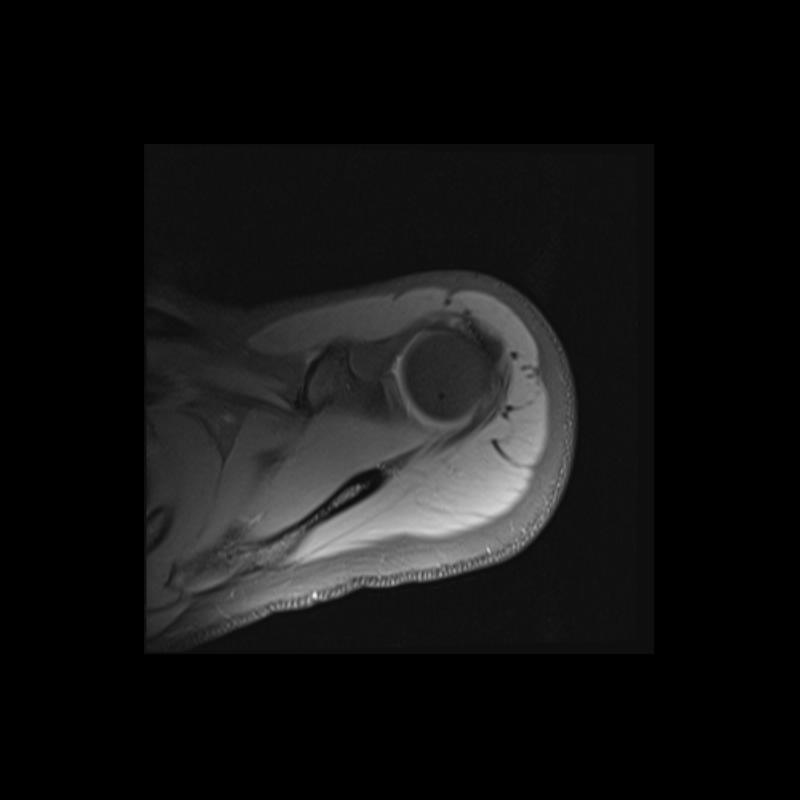

Shoulder MRI Anatomy